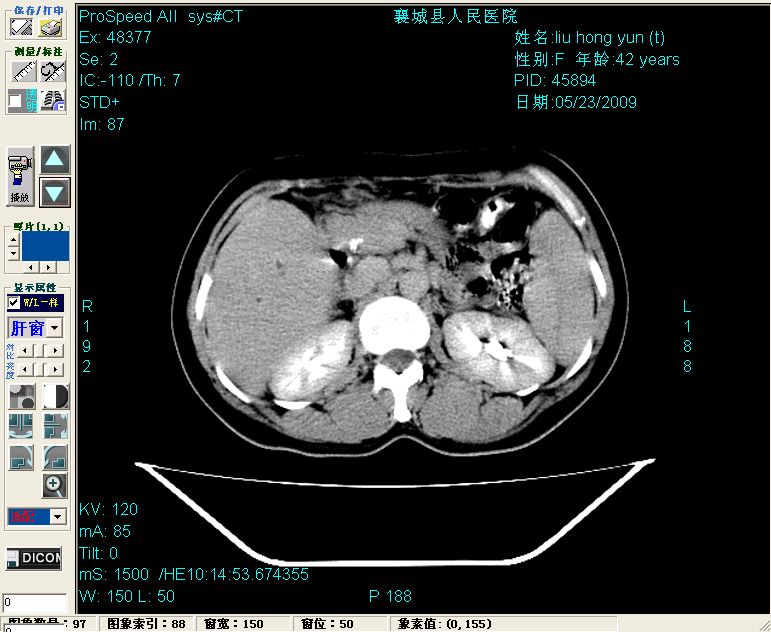

增强:

增强动脉期前述低密度区轻度早其强化,门脉期强化程度显著增高,延期扫描强化程度下降,但仍为相对高密度影

2左肝及右肝前叶表现考虑胆囊摘除术后所致的肝动门脉瘘形成,慢性纤维组织炎性增生.不完全除外左肝胆管细胞癌